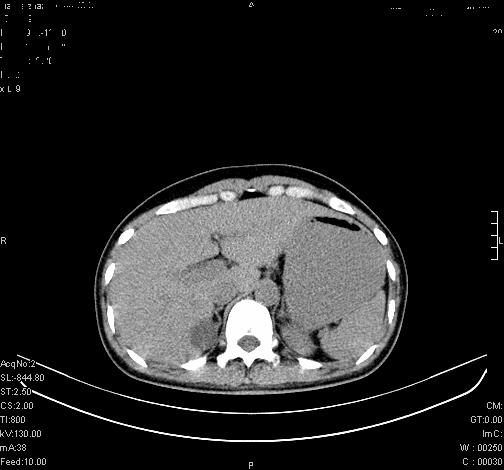

标题: CL0340:【】肾上腺囊肿,比较典型。

患者为年轻女性,查体发现右侧肾上腺囊性占位。无临床体征。

这么漂亮的图像,一看一目了然。典型的右侧肾上腺囊肿,周围有钙化。感谢搂主!

“肾上腺囊肿组织学分为4类:1)内皮细胞性,2)假性囊肿,3)寄生虫性,4)上皮细胞性。其中内皮细胞性最为常见。假性囊肿多为肾上腺内出血后遗留囊腔,囊壁无上皮细胞。寄生虫性多为包虫病引起。上皮性则很少见。”

这么明显的弧形钙化,多考虑包虫病所致的寄生虫性囊肿。

右侧肾上腺囊性密度灶囊壁有钙化。考虑肾上腺囊肿,结核?

右侧肾上腺囊肿,周围有钙化。